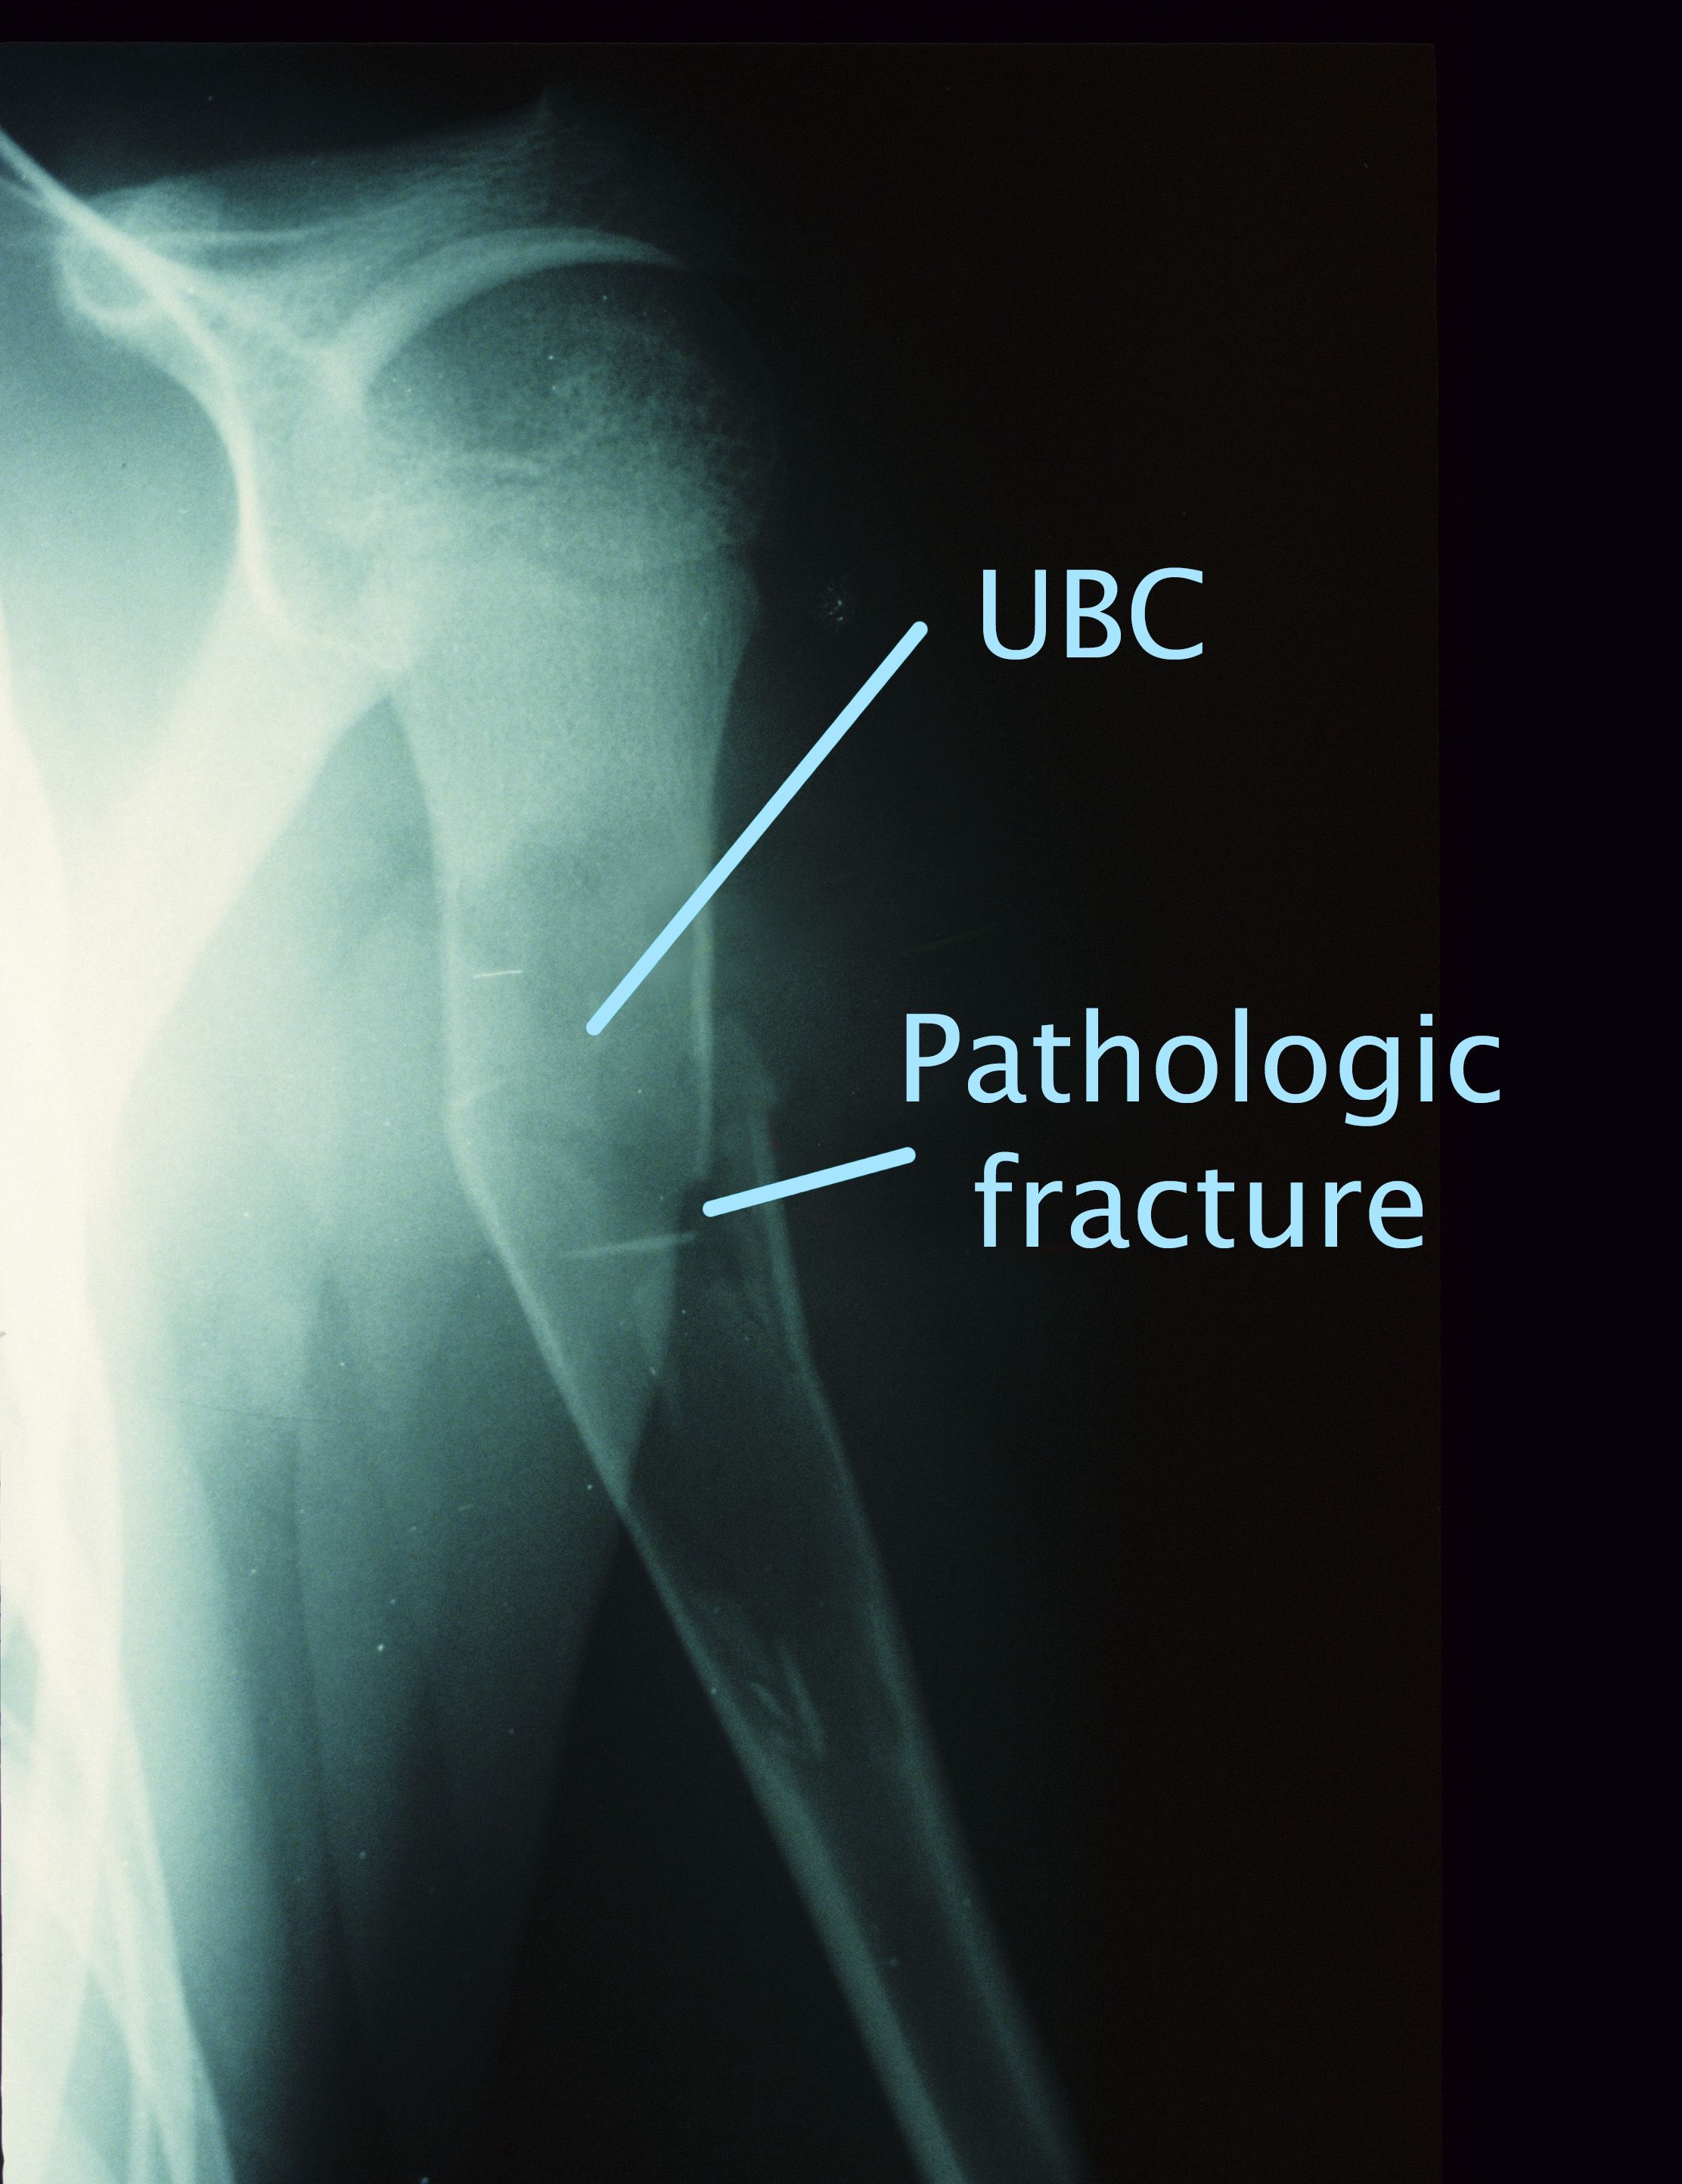

If you think you're an anatomy buff who knows the difference between the tibia and the fibula, this is th. Unicameral Bone Cysts Orthoinfo Aaos Source: orthoinfo.aaos.org